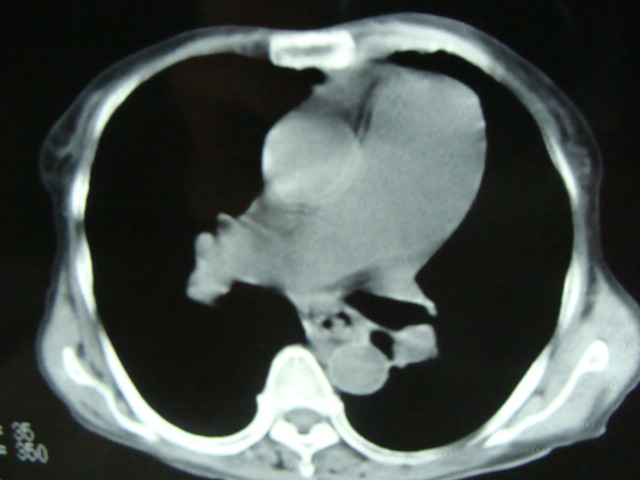

标题: CT13799:风心?肺动脉发育异常?

xxx女.72岁,胸闷不适,一侧下肢水肿.肺窗没见异常.不上传.

肺动脉根部,右室增宽;肺门小;是什麽征象///

右肺动肺截断.肺动肺脉高压

主肺动脉扩张,腹水.

考虑:1、肺动脉高压(原因?);